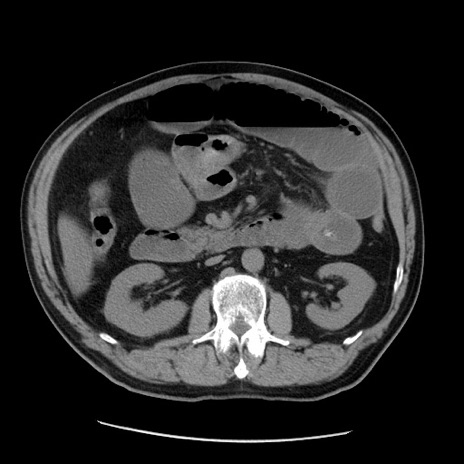

症例20(横断像)

【症例】 60歳代男性

【主訴】 腹部膨満、嘔吐

【現病歴】5日前頃より倦怠感を認め食事量減少し4日前の朝嘔吐、食事摂取困難となった。 3日前近医受診し点滴施行され整腸剤などを処方された。 当日他院を受診し、腹部膨満著明、炎症反応の上昇(CRP10.8、WBC11200)あり、紹介受診となる。

【身体所見】 意識JCS1 受け答えがはっきりしないBP 111/57mHg、 P 67bpm、、BT35.2°C、SpO2 97%(RA)、 腹部:膨隆、打診で鼓音あり、全体的に圧痛有り、腸蠕動音(-)、反跳痛ははっきりせず。

【データ】WBC 11400、CRP 14.20